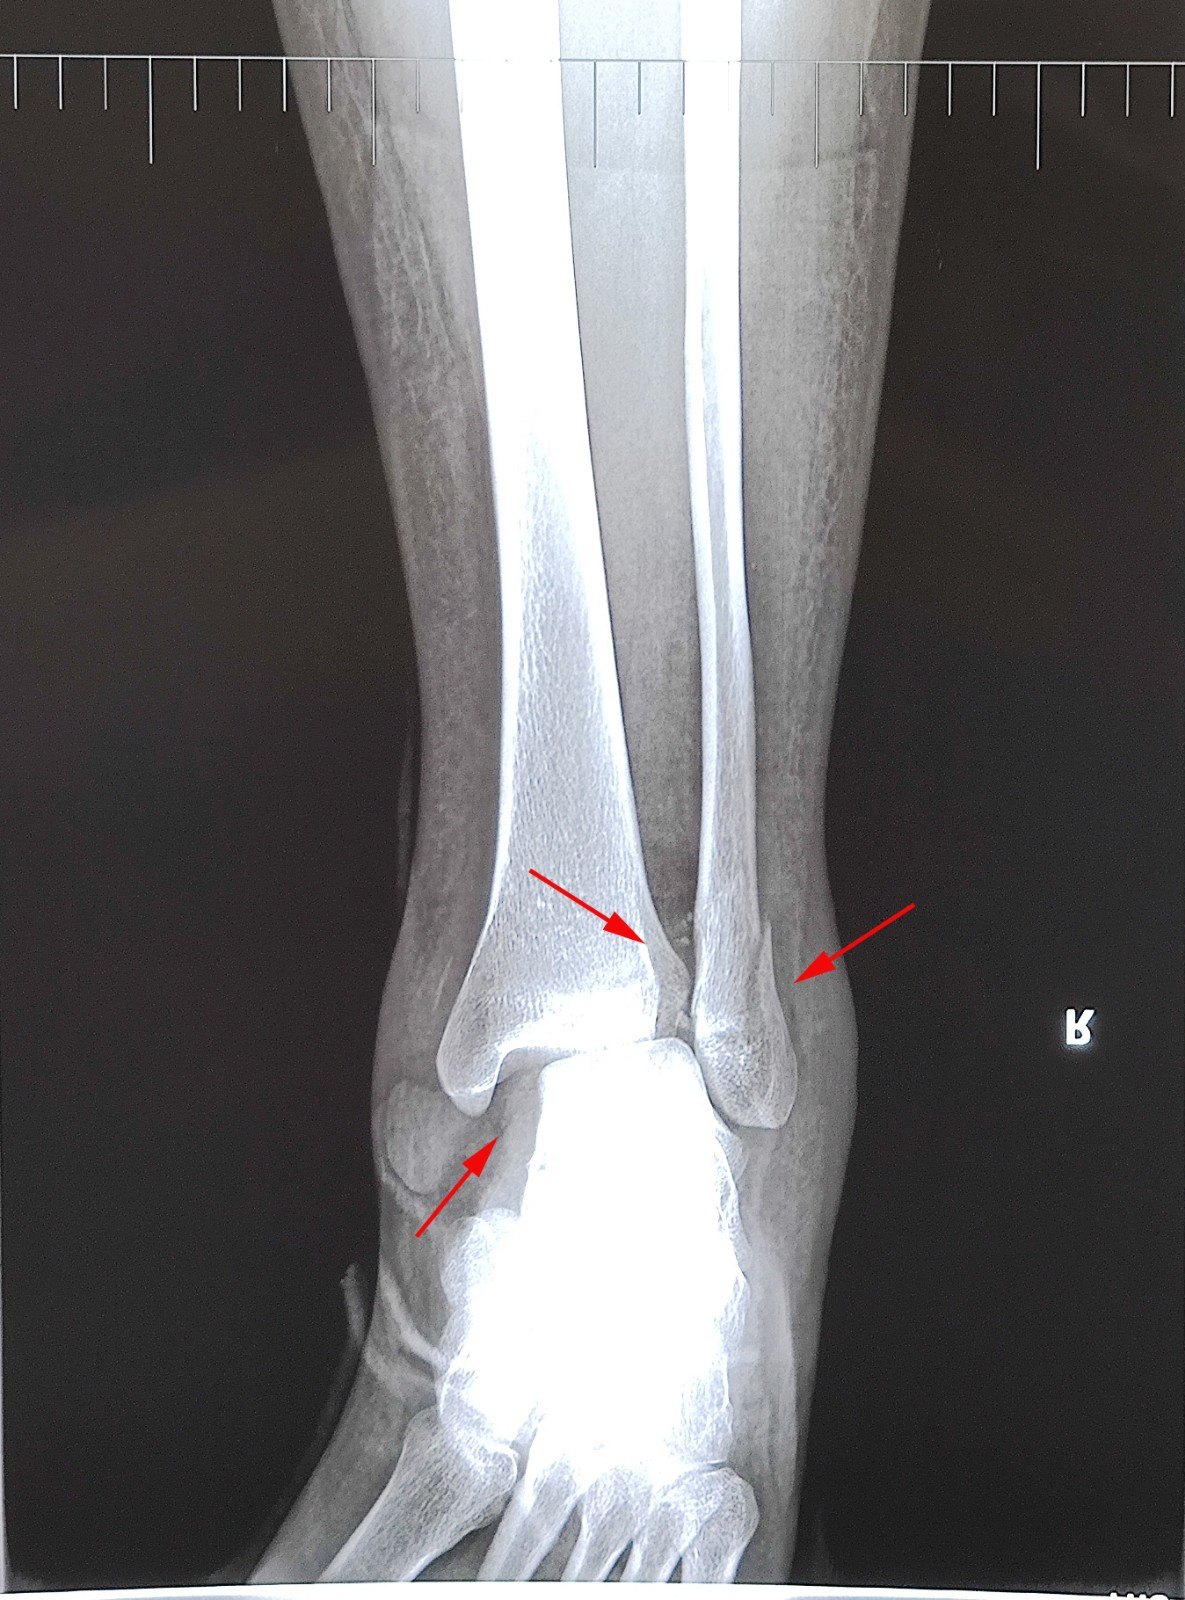

2个典型病例教会你踝部骨折外固定 医学界 助力医生临床决策和职业成长

左腓骨骨折 X线影像 医学影像 医学图谱 37度医学网